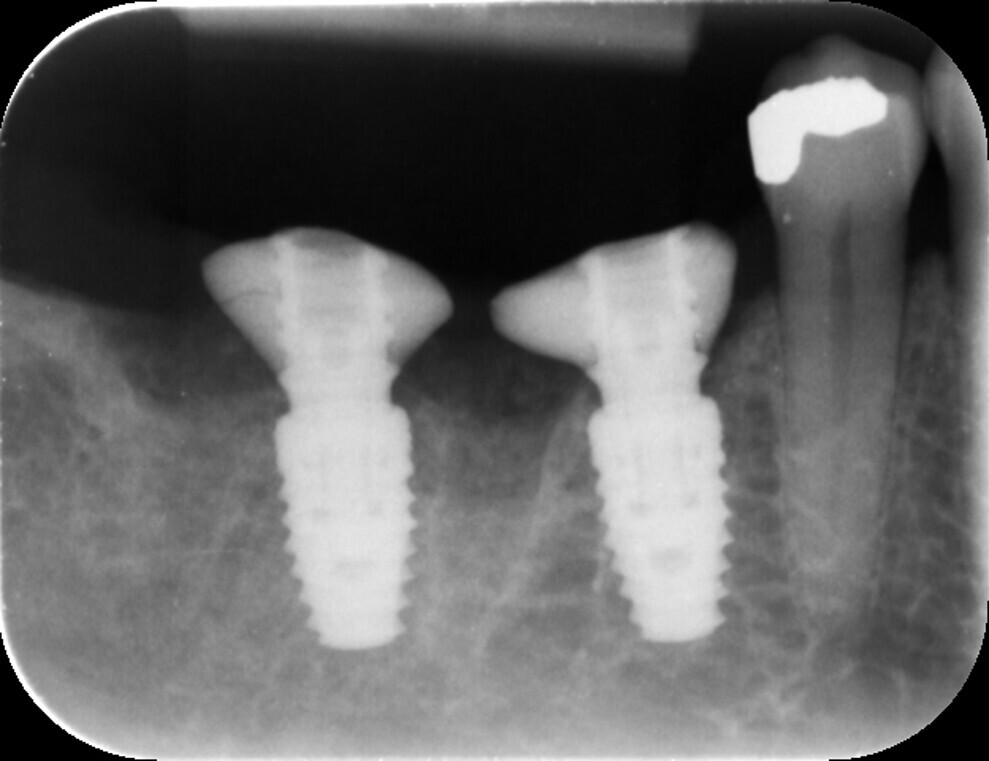

Fig. 12: Post-op radiograph.

After a healing period of three months, the Medit i700 intra-oral scanner was used to record the implant position and soft-tissue profile, ensuring optimal prosthetic planning and precise restoration (Fig. 12). The implant crowns were constructed using custom milled titanium abutments with a zirconia crown. Care was taken to ensure that any zirconia in contact with the tissue was polished rather than glazed to promote optimal soft-tissue health.